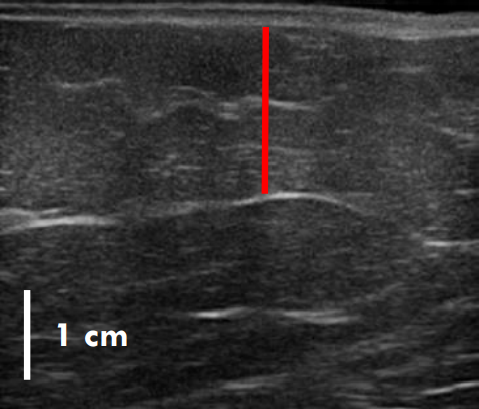

트루스컬프 아이디 시술 전, 12주 후 초음파를 비교한 사진입니다.

레드 라인이 지방층의 두께입니다.

앞서 보여드린 사례의 경우 시술 전과 비교했을 때 약 36% 정도 지방이 감소한 결과를 볼 수 있는데요.

이 정도의 지방량을 줄이려면 일반적인 운동, 식이요법만으로는 한계가 있지요.